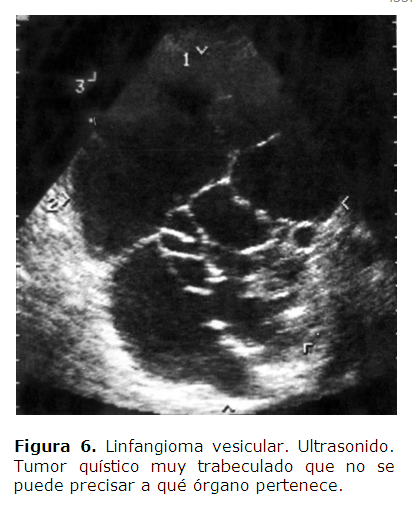

Puede verse una imagen que recuerda un "panal de abejas" o una "esponja". En ocasiones, cuando el linfangioma es grande, la vesícula biliar no se puede observar por quedar envuelta o comprimida por el linfangioma y solamente se observa una imagen quística en la proyección de la vesícula biliar como ocurrió con este caso (Figura 6).

Puede informar una imagen compleja o una masa hipoecoica, bien circunscrita con finos y delicados tabiques en su interior, además, de localizarlo en la víscera, bazo, vesícula e hígado como en nuestros casos, y facilitar las dimensiones del quiste.2,3,6,7,11,12